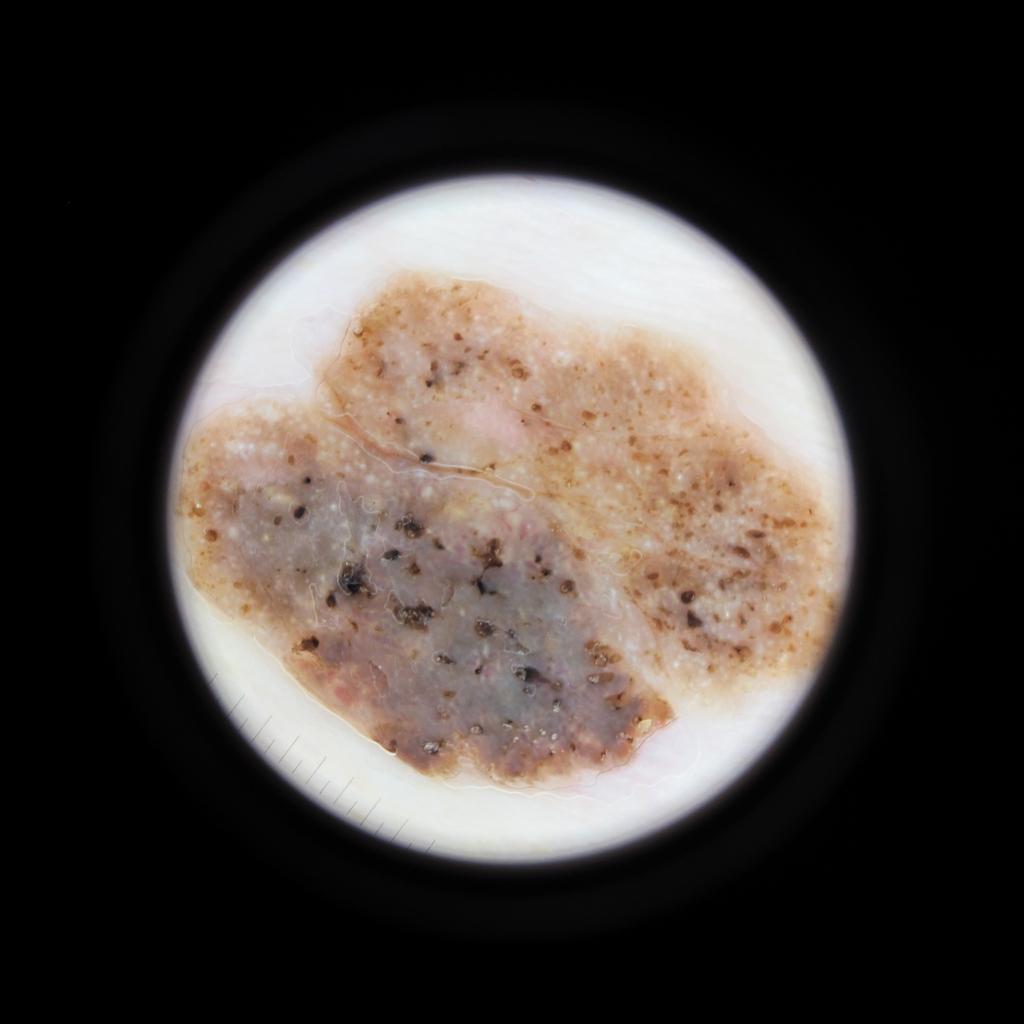

Case: 34